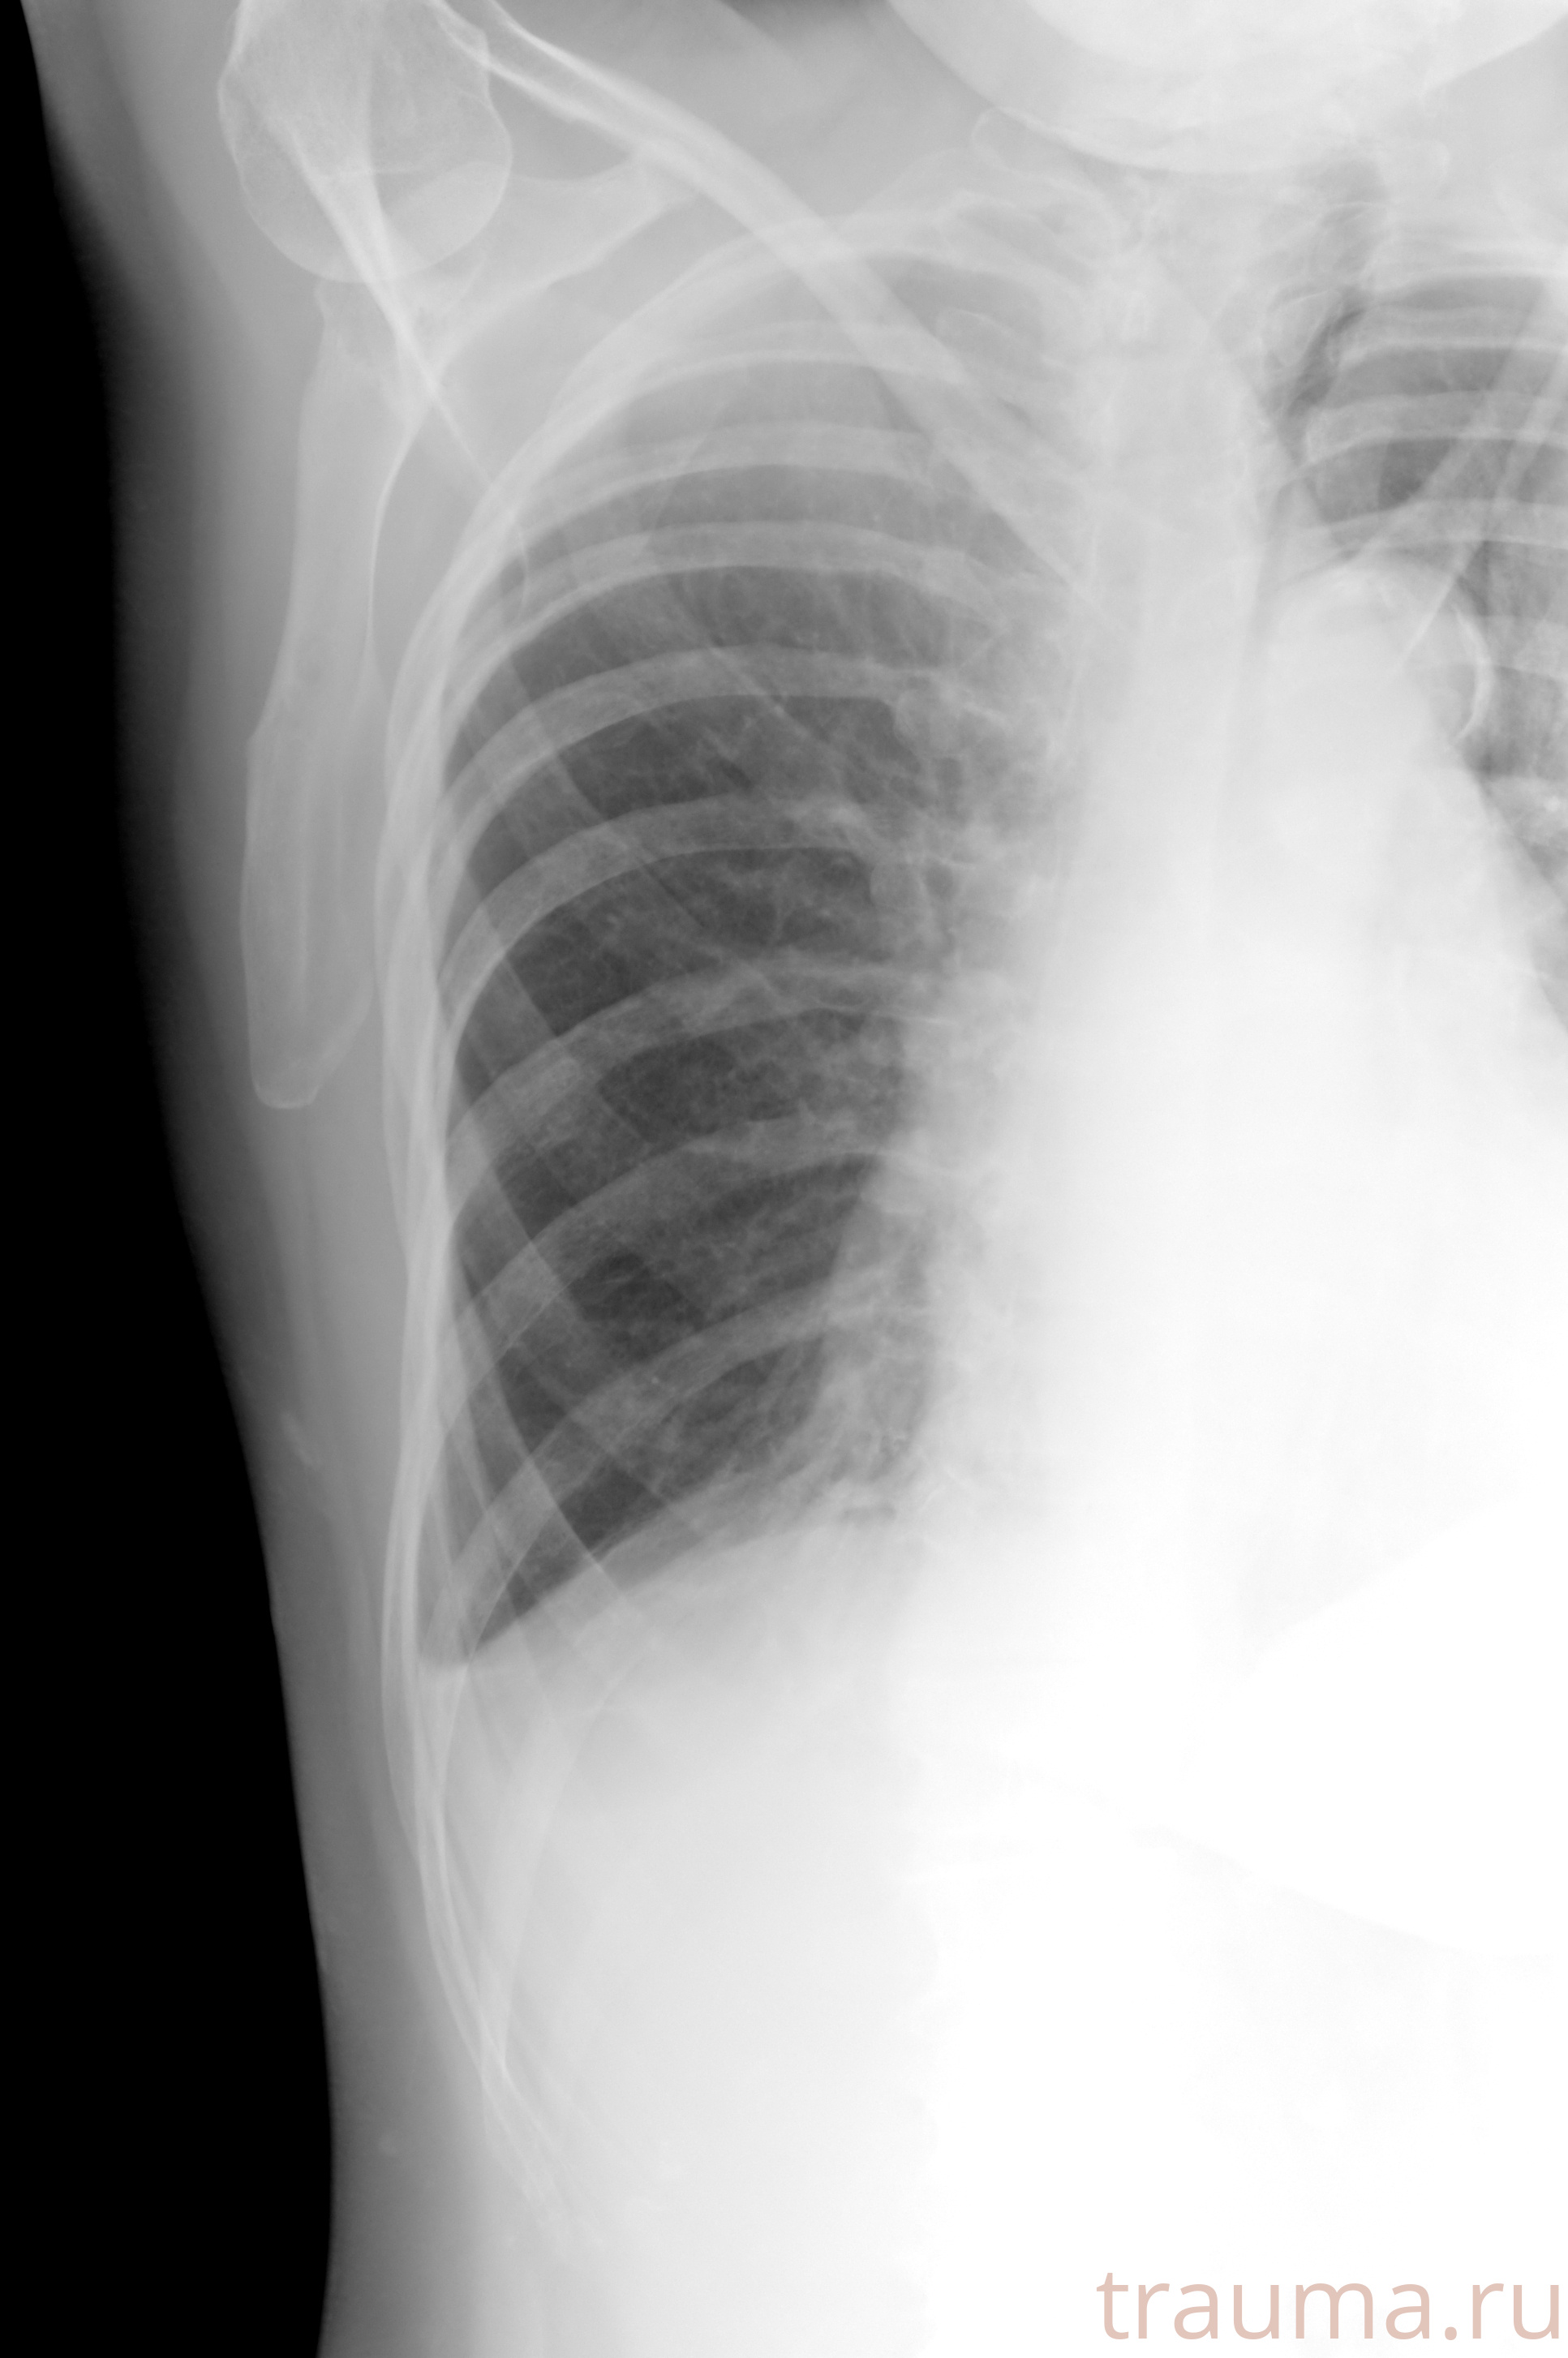

Рентгенограммы

Рентген на дому: по вашему адресу приезжает врач-рентгенолог, травматолог-ортопед с мобильным рентгеновским аппаратом, проводит диагностику травмы или заболевания, делает необходимые рентгенограммы, дает рекомендации по дальнейшему лечению. Получить качественные снимки в домашних условиях возможно благодаря уникальной методике, разработанной МосРентген Центром для института  Склифосовского

Яркость: 1   Контраст: 1   Инвертировать: 0 Увеличение: 1

Перетаскивайте мышь вверх/вниз для контраста, влево/право для яркости. Прокрутка колесом изменяет масштаб. Нажмите Сбросить для возврата к исходному изображению. При увеличении держите мышь в той области, которую хотите рассмотреть.